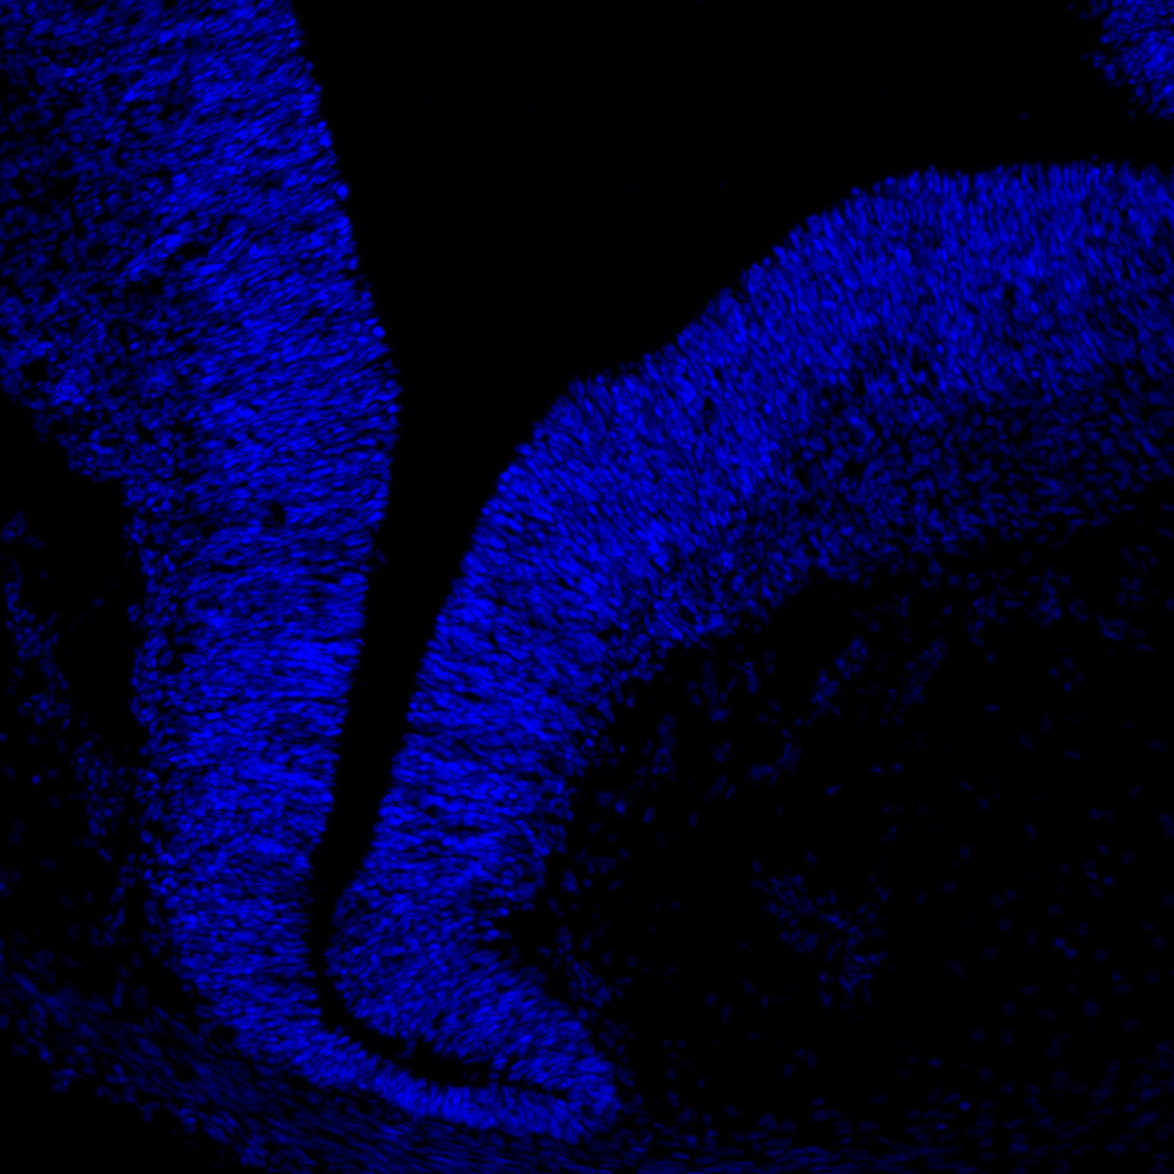

DAPI

6PCW human midbrain